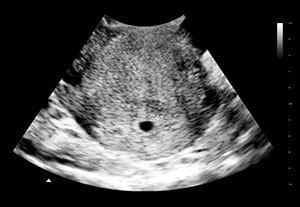

5周双胞胎假怀孕B超图

¥60.00 -

假怀孕7周b超图

¥60.00 -

怀孕8周b超图片

¥60.00 -

假怀孕4周b超图

¥60.00 -

假怀孕5周b超图

¥60.00 -

怀孕10周彩超单子

¥60.00

关键在于无懈可击的逼真呈现。我们的打印件采用正宗医用光面纸,搭配数十款 4 周至足月的超写实设计(含双胎、三胎模板),为整蛊的可信度筑牢根基。

无论是愚人节的经典名场面,还是极具话题性的惊喜宣告,这款假超声波图片都足以让最谨慎的对象也深信不疑。用作影视道具或精心策划的整蛊方案,它都是助你荣登 “整蛊大师” 宝座的终极装备。实时预览自定义细节,数字版即时获取 —— 你专注创意发挥,逼真效果交给我们搞定。

医用级光面工艺打印!6×8 厘米高端光面照片纸制作,还原照片级清晰画质。专为影视道具、节日恶搞、创意纪念等场景设计!